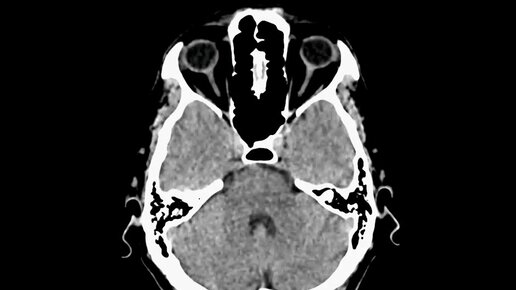

Что покажет КТ головного мозга (видео)